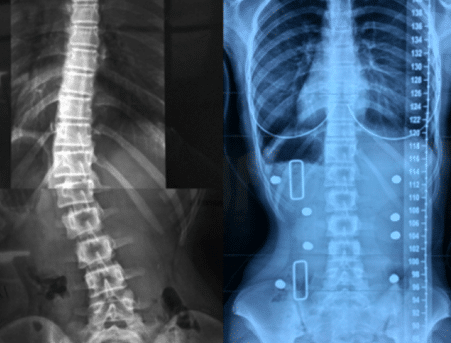

تقييم اعوجاج العمود الفقري بعد 6 أشهر بدون الحزام: أهم مؤشر لتحديد نجاح العلاج يُعد اعوجاج العمود الفقري لدى المراهقين من أكثر الحالات التي تُقلق الأهل، خاصة عند بدء العلاج بالحزام الطبي (الدعامة). وغالبًا

التنبؤ بنتائج حزام اعوجاج العمود الفقري :الفرق بين الأشعة داخل الحزام وخارجه يُعد اعوجاج العمود الفقري عند المراهقين من أكثر حالات التشوهات الشائعة خلال مرحلة النمو، ويُعرف طبيًا باسم “الجنف مجهول السبب عند المراهقين”.